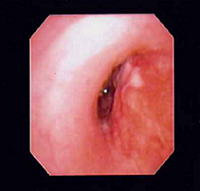

The etiology of this acute kidney injury was believed to be multifactorial and included the dosage increase of the glycopeptide antibiotic and possible renal involvement in undiagnosed GPA. During the onset of acute renal failure, the patient appeared well-hydrated, and urinalysis results and urine output remained normal. The patient underwent a renal biopsy, along with bronchoscopy to evaluate hemoptysis and the airway. During the bronchoscopy, a 3.6-mm outer-diameter bronchoscope was unable to be advanced past the right mainstem bronchus due to external compression. In order to prevent possible bleeding, endobronchial biopsy and bronchoalveolar lavage were not performed.

Figure 1. A round cavitary lesion was visible in the right upper lobe.

Figure 3. Compression of right mainstem bronchus was noted during bronchoscopy.